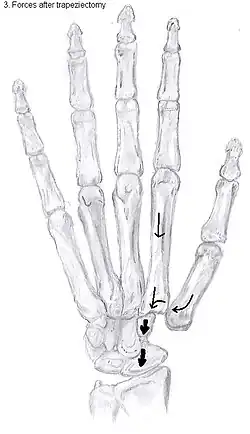

Trapeziectomy

During trapeziectomy,[30] the trapezium bone is removed without any further surgical adjustments. The trapezium bone is removed through an approximately three centimeter long incision along the lateral side of the thumb. To preserve surrounding structures, the trapezium bone is removed "by splitting" it into pieces.

An empty gap is left by the trapeziectomy and the wound is closed with sutures. Despite this gap, no significant changes in function of the thumb are reported.[27] After the surgery, the thumb will be immobilized with a cast.

Metacarpal osteotomy

The aim of metacarpal osteotomy is to change the pressure distribution on the TMC joint. The hope is that this will slow the pace of development of osteoarthritis. There is no evidence that this procedure can modify the natural course of TMC OA. Osteotomy may be considered for people with mild arthritis.[24]